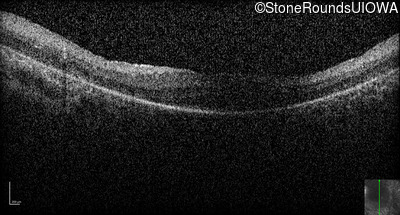

Optical Coherence Tomography - Right -

No Light Perception

Exemplar

Optical Coherence Tomography - Left -